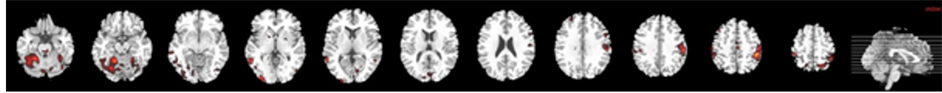

The processing of neutral faces compared with baseline (21 foci) activated significantly: frontal areas (right medial frontal gyrus, right frontal inferior, bilateral precentral gyrus), temporal areas (right middle temporal and right temporal superior), parietal regions (right supramarginal gyrus, left superior parietal lobule, left postcentral gyrus), bilateral cerebellum, and subcortical area (left putamen and right globus pallidus) cerebellum (cluster p < 0.001, false discovery rate [FDR] p < 0.001; Table 3, Figure 3(a)).

2.4.2. Processing 100% Fearful Faces

The processing of fearful faces compared with baseline (24 foci) was associated with significant increase of BOLD signal in: the visual regions (left inferior occipital gyrus and left fusiform gyrus), temporal areas (right middle temporal and inferior gyri), parietal regions (left parietal superior, bilateral postcentral gyri, bilateral angular gyrus), and the bilateral cerebellum (cluster p < 0.001, false discovery rate [FDR] p < 0.001; Table 3, Figure 3(b)).

Figure 3. Brain maps of neural activation in response to both neutral (a) and 100% fearful facial expressions (b) compared with fixation cross in the healthy control group.

Before therapy of B.D. recruitment was larger in the left hemisphere, both with neutral and fearful faces. In response to neutral faces visual cortex was significantly activated, including calcarine and fusiform gyrus. Before treatment was provided, perception of 100% fearful expressions recruited cerebellum, precentral gyrus and visual regions but not amygdala. We found that processing of fearful faces in healthy controls was associated with increased activation in visual brain regions including fusiform gyrus, temporal and parietal areas and bilateral cerebellum; which again corresponded with robust neuroimaging data.